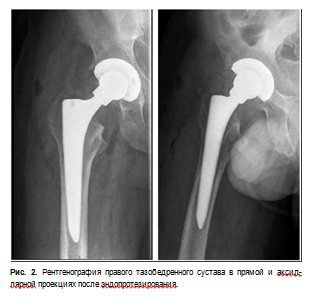

В травматологическом отделении выполнен рентгеновский снимок обоих тазобедренных суставов, выявлен асептический некроз головки бедренной кости.

С целью дообследования выполнена магнитнорезонансная томография тазобедренных суставов (рис. 1).

Учитывая клинические проявления (болевой синдром, нарушение функции правой нижней конечности, отсутствие опорности из-за выраженного болевого синдрома), рентгенологические данные (асептический некроз головки бедренной кости справа) выставлен диагноз правосторонний асептический некроз головки бедренной кости, что является показанием к оперативному лечению.